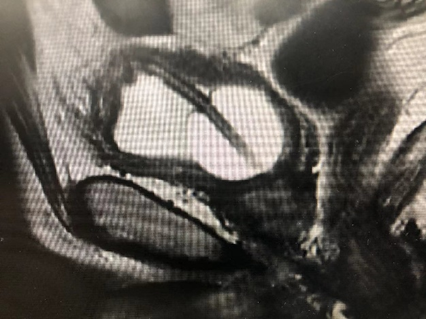

病例五,52岁女性,发现右肾肿物1月。CTU提示右肾癌7.7cm×6.8cm×11.6cm,伴MayoII级下腔静脉癌栓,长6.5cm。既往乙肝肝硬化。贫血。行机器人辅助腹腔镜右肾根治+下腔静脉瘤栓取出术,术者:张洪宪教授。术中发现肿瘤生长迅速,瘤栓较术前3天的影像学检查相比有进展,术中探查发现瘤栓已生长至下腔静脉肝后段,且质地极为糟脆,由于肝后下腔静脉不容易进行近心端阻断,遂采用不阻断近心端方法:充分游离肝后下腔静脉后,术中切开下腔静脉,采用“Milk”技术,用纱布沿下腔静脉近心端将下腔静脉瘤栓向下全部挤压出下腔静脉管腔,之后用纱布压迫下腔静脉近心端做临时阻断,同时缝合下腔静脉壁。